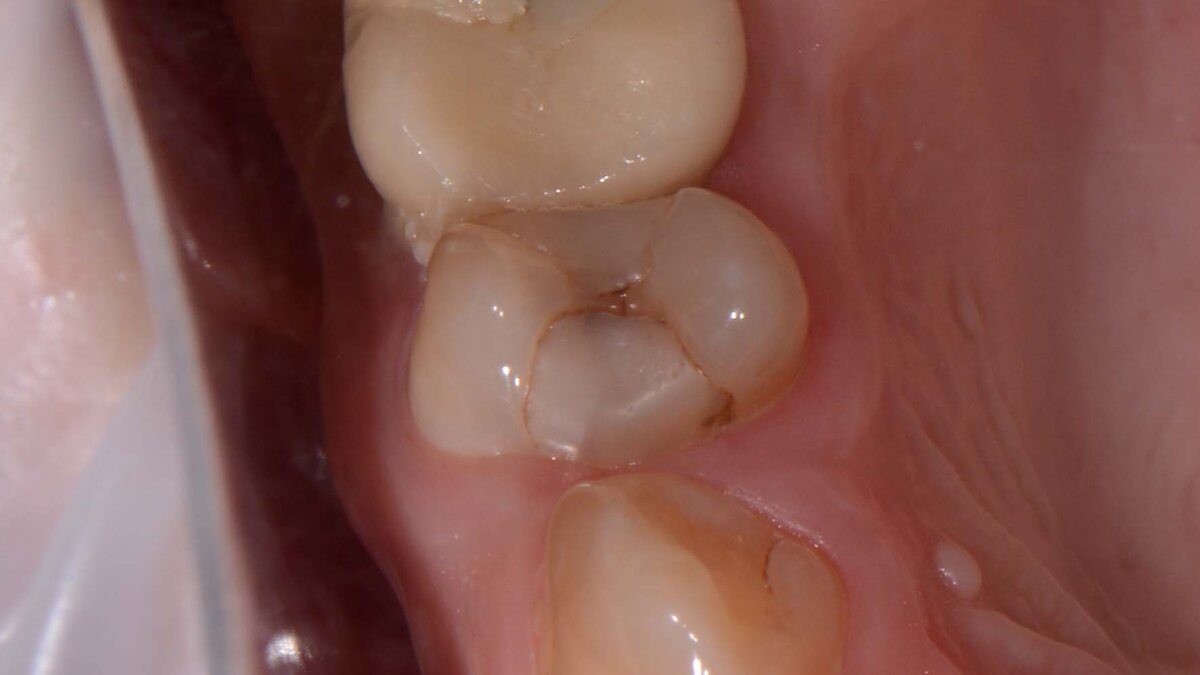

Стоматолог оценивает именно состоятельность пломбы, а не просто ее наличие в зубе. Если пломба проелась, стерлась, если нарушено краевое прилегание, если пломба имеет нависающий край и вредит десне, если есть кариес по границе пломба-зуб, то эта пломба подлежит замене, потому что зуб не жует как надо и незаметно разрушается. Особенно это касается депульпированных зубов (без нерва), потому что они никак не могут просигнализировать о наличии проблемы.

И для наглядности фото несостоятельных пломб: